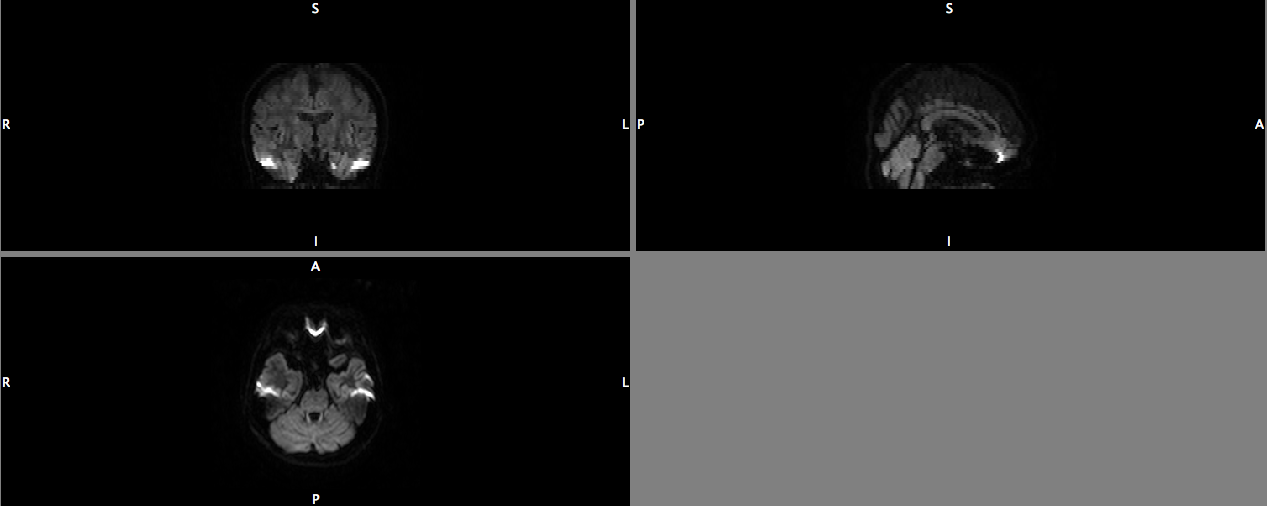

Would like to get some opinions and advice from helpful contributors on

this forum regarding the quality of the DTI data that I have been asked to

process. I have attached some screenshots in this post so it illustrates my

question.

1) The datasets seem to have a similar problem which I'm guessing, is due

to susceptibility artefacts. It seems to be a recurrent issue around the

same areas and slices (around x=125-130, y=119-122, z=8-10).

Based on the images, what would be the ideal way forward? Would using the

RESTORE function help in this case?